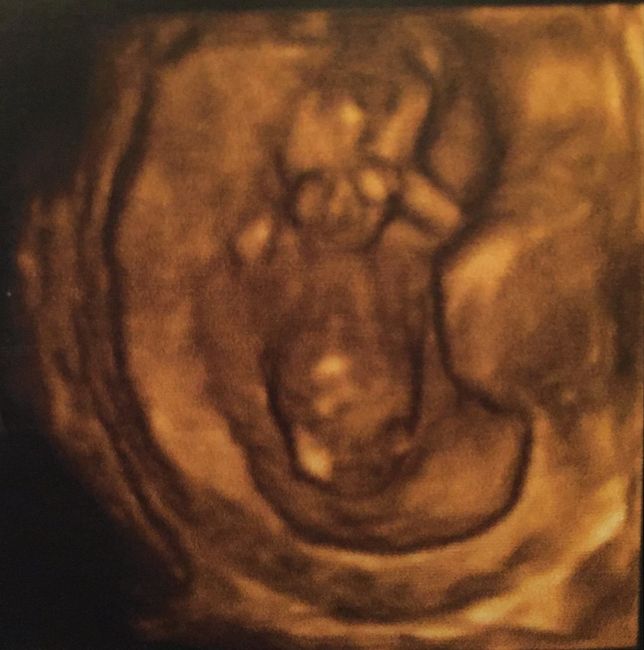

Buongiorno mammine...vi volevo presentare l'amore della mia vita Davide...mercoledì abbiamo fatto la morfologica e a 23+5 il mio torello pesava 621 grammi per 28 cm...il...